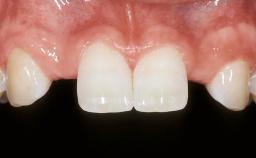

| Case Type | Single-Tooth Space |

| Jaw | Maxilla |

| Area | Anterior |

| # of Teeth | 1 |

Esthetic Risk Assessment

| Esthetic Risk Factors | Low | Medium | High |

|---|---|---|---|

| Medical Status | Healthy | Compromised | |

| Smoking Habit | Non-smoker | Light smoker (< 10 cigarettes per day) | Heavy smoker (>= 10 cigarettes per day) |

| Patient's Esthetic Expectations | Low | Medium | High |

| Lip Line | No exposure of papillae | Exposure of papillae | Full exposure of mucosa margin |

| Periodontal Phenotype | Low-scalloped, thick | Medium-scalloped, medium-thick | High-scalloped, thin |

| Shape of Tooth Crowns | Rectangular | Triangular | |

| Infection at Implant Site | None | Chronic | Acute |

| Bone Level at Adjacent Teeth | <= 5 mm to contact point | 5.5 to 6.5 mm to contact point | > 7 mm to contact point |

| Prosthodontic Status of Neighboring Teeth | Virgin | Restored | |

| Width of Edentulous Span | 1 tooth (>= 7 mm) | 1 tooth (< 7 mm) | 2 teeth or more |

| Soft Tissue Anatomy | Intact | Defective | |

| Bone Volume | Horizontally and vertically sufficient | Horizontally deficient | Deficient vertically or deficient vertically AND horizontally |